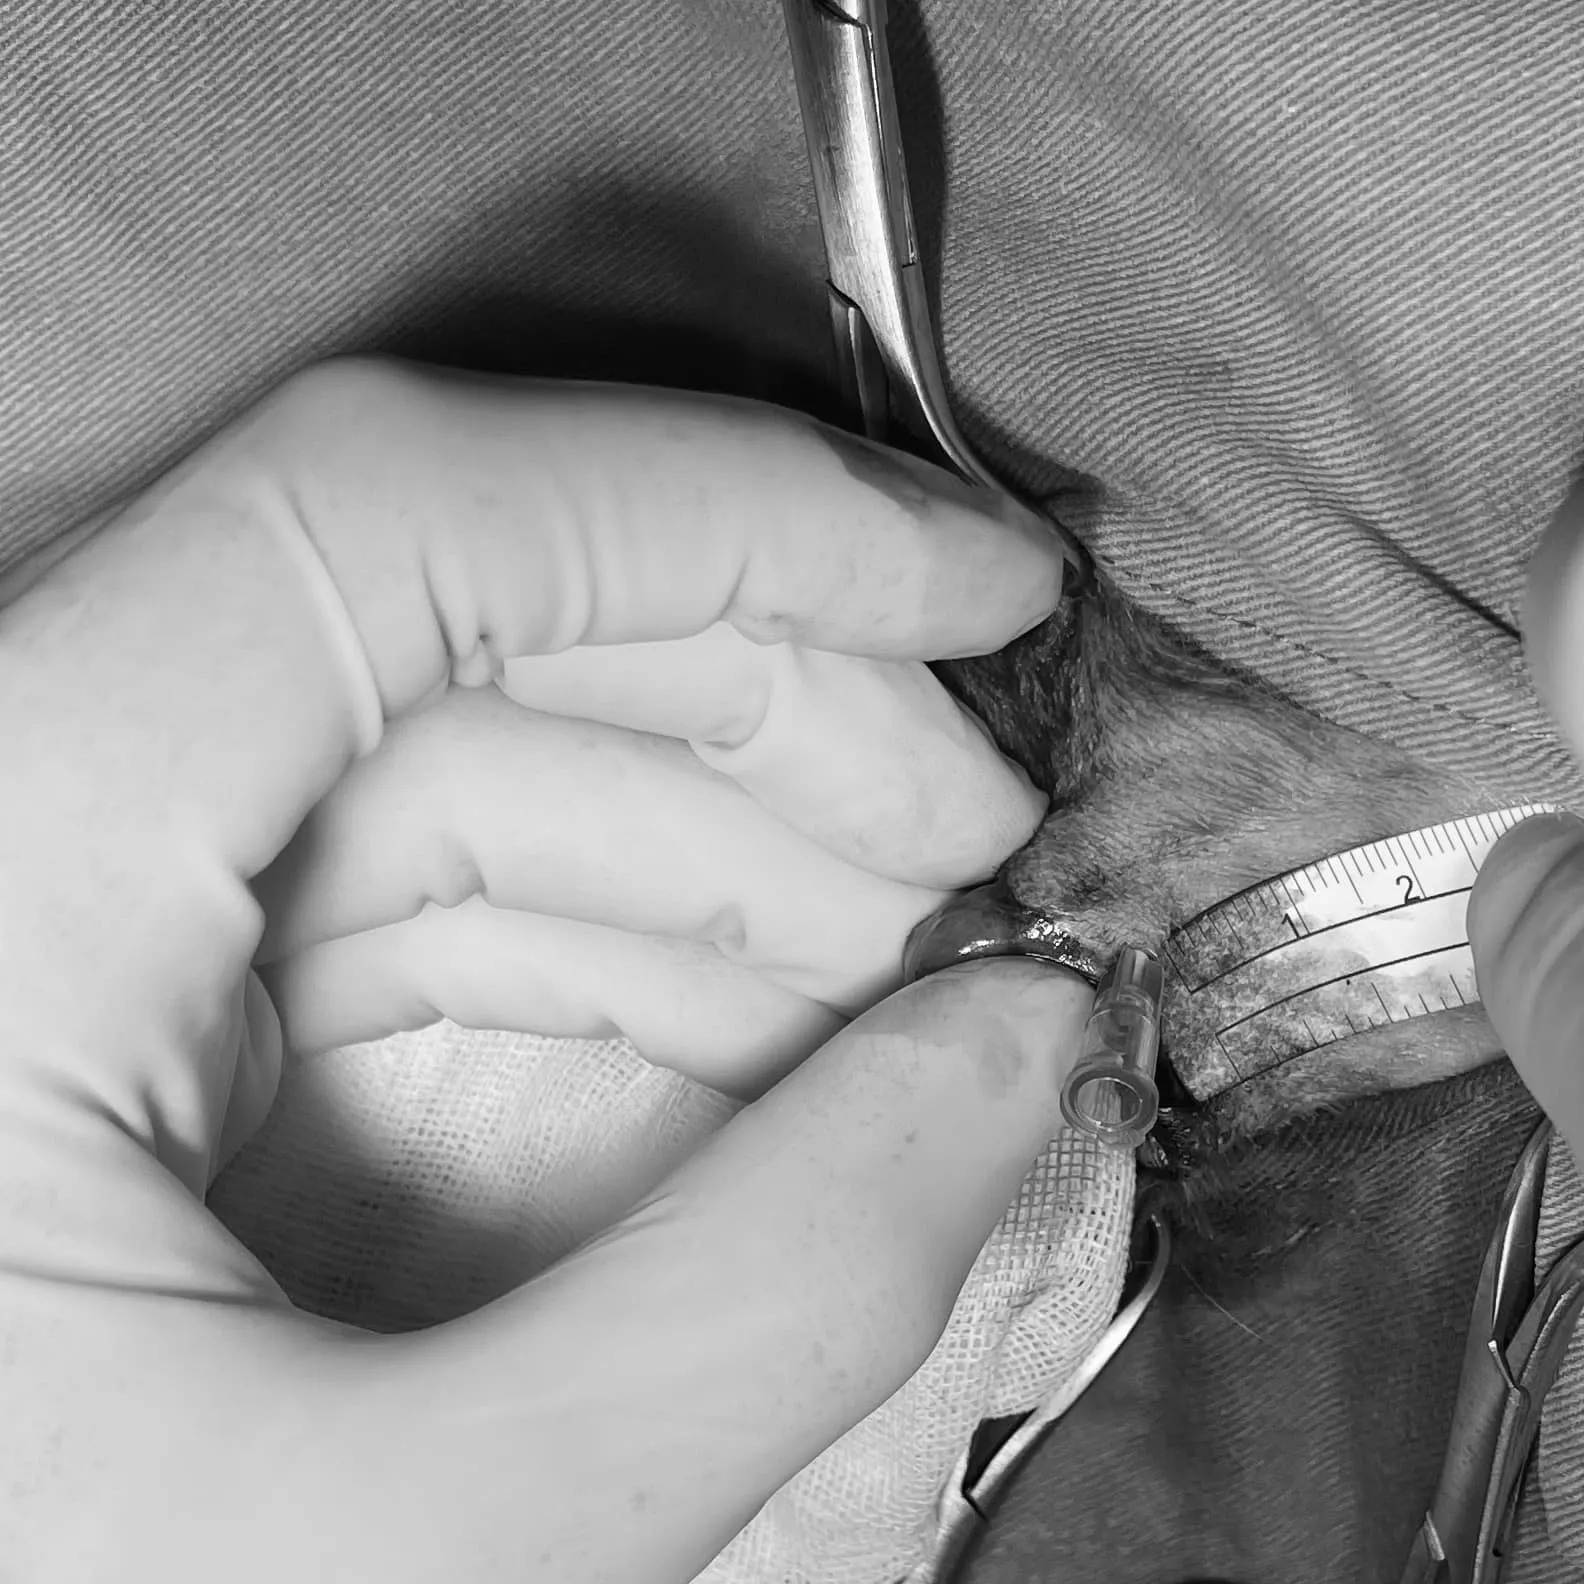

肉眼看上去腫瘤範圍並不大,但我們為了預防復發,在可見腫瘤邊緣,不論是皮膚面還是口腔黏膜面都往外預留了1-1.5公分的切除邊界,如圖所示切除後範圍是很大的,倘若直接縫合,狗狗以後口腔是絕對張不開的!

利用針頭進行切創範圍的立體定位

以手術記號筆標示出需要切除的區域,明顯比單純切除腫瘤有較大的範圍!